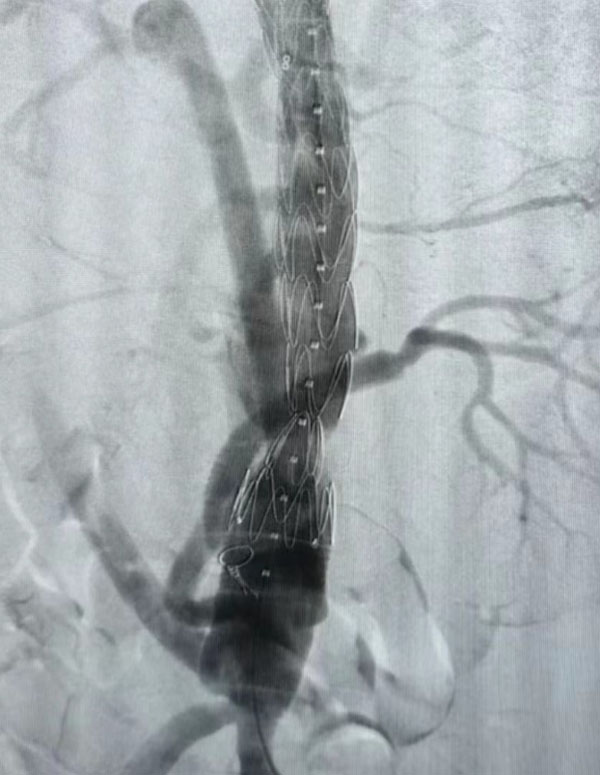

同期另一台升主动脉置换+全主动脉弓置换+胸主动脉覆膜支架腔内隔绝术”正在开展,该病例为一名A型主动脉夹层患者。在主动脉弓及分支成功游离心脏停跳后,心外科负责人赵永波转场为患者完成了血管置换,心脏复跳成功,止血彻底随后谈凌凌主治医师、侯五辉主治医师为患者进行胸主动脉腔内修复。下午2点左右台手术成功结束。通过现场视频直播,手术同时,手术人员与大会现场的专家就影像评估、手术策略、手术器械的选择及操作技巧等多个环节进行了互动讨论,学术气氛热烈,大会主席及与会代表给予我院高度评价。紧接着,手术团队又一名79岁腹主动脉瘤患者进行了腹主动脉腔内修复手术,效果良好,同样受到与会专家的好评。

全主动脉弓置换